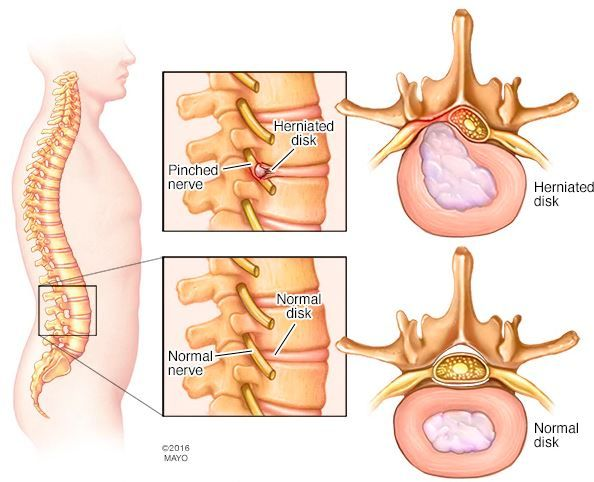

什么是腰椎間盤突出癥?

腰椎間盤突出癥又稱腰椎間盤纖維環(huán)破裂髓核突出癥。是在椎間盤發(fā)生退行性變之后,在外力的作用下,纖維環(huán)破裂髓核突出刺激或壓迫鄰近的神經根、脊髓或血管等組織,從而產生腰部疼痛、一側下肢或雙下肢麻木、疼痛、無力等一系列臨床癥狀的一種病變。癥狀一般為突發(fā),也可以隱匿發(fā)展。